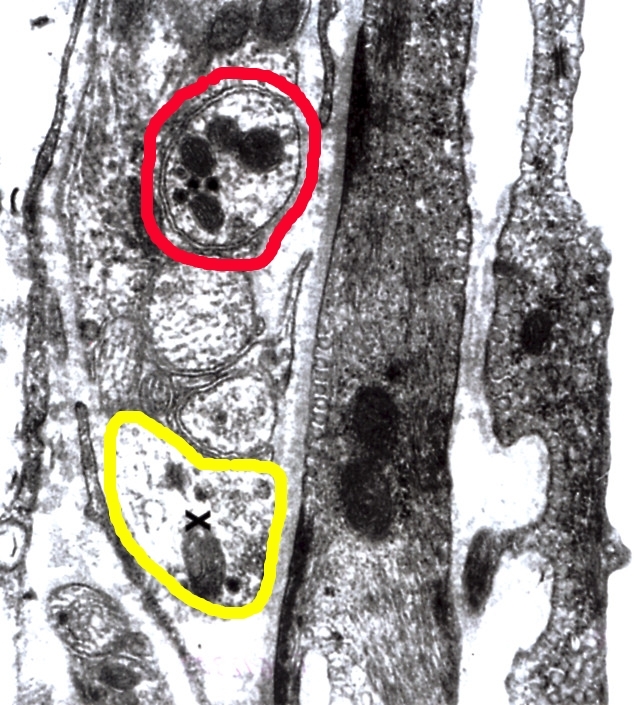

Bild stellt rotes Knochenmark dar

X = Megakaryozyt

kann jemand die restlichen Zellen bennen?

Zu dein Knochenmarkbild sieht es aus als ob die Zelle im Roten Kreis ein Normoblast ist (ein vorlauf Stadium von ein Erythrozyte die hier noch Kernhaltig ist). Bestimmung von Knochenmark ist aber nicht so einfach weil da fast alle Zellen in ein anderes Differenziertes Stadium sind.

Die Megakaryozyt ist richtig denke ich.

Bild zeigt eine Arteriolenwand

gelb = Nervenendigung in der Adventitia

was ist rot ??

und wer kann mir sagen, wo sich hier die Basallamina befindet ?

rot = Megakaryozyt

gelb = Erythrozyt-Vorläufer

blau = ??? (ist das ein reifer Erythrozyt? Ich sehe keinen Zellkern)

Zum Knochenmark. Mein Bild stammt nicht vom Knochenmark. Es kommt aus ein Mausfetus Leber. Da wird zuerst das Blut gebildet. Ob es Blut oder Hepatozyten sind weis ich nicht. Dein Roten Kreis ist eine Megakaryoblast oder -zyte, Blau kann eine reifere Erytrozyte sein aber auch ein Normoblast wovon den Kern nicht angeschnitten ist. Bleibt also unsicher.